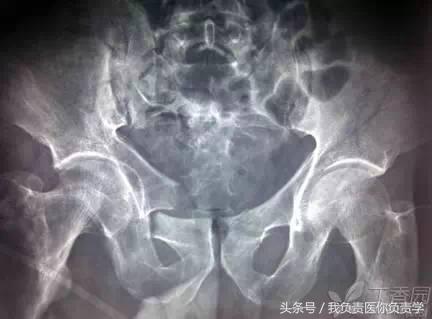

3. Malgaigne 骨折(玛尔盖涅骨折)

指存在垂直旋转不稳的纵向骨盆骨折,骨盆后环有骶髂关节脱位或髂骶骨的纵向骨折,骨盆前环可累计双侧耻坐骨支、耻骨联合等,常合并尿道损伤,需手术治疗。该骨折首先由法国医生 Malgaigne 描述,故此得名。